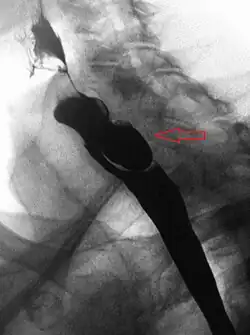

Lateral X-ray of a Zenker's diverticulum

A combination of the simple barium swallow and a thorough endoscopy will normally confirm the diverticulum.[4]